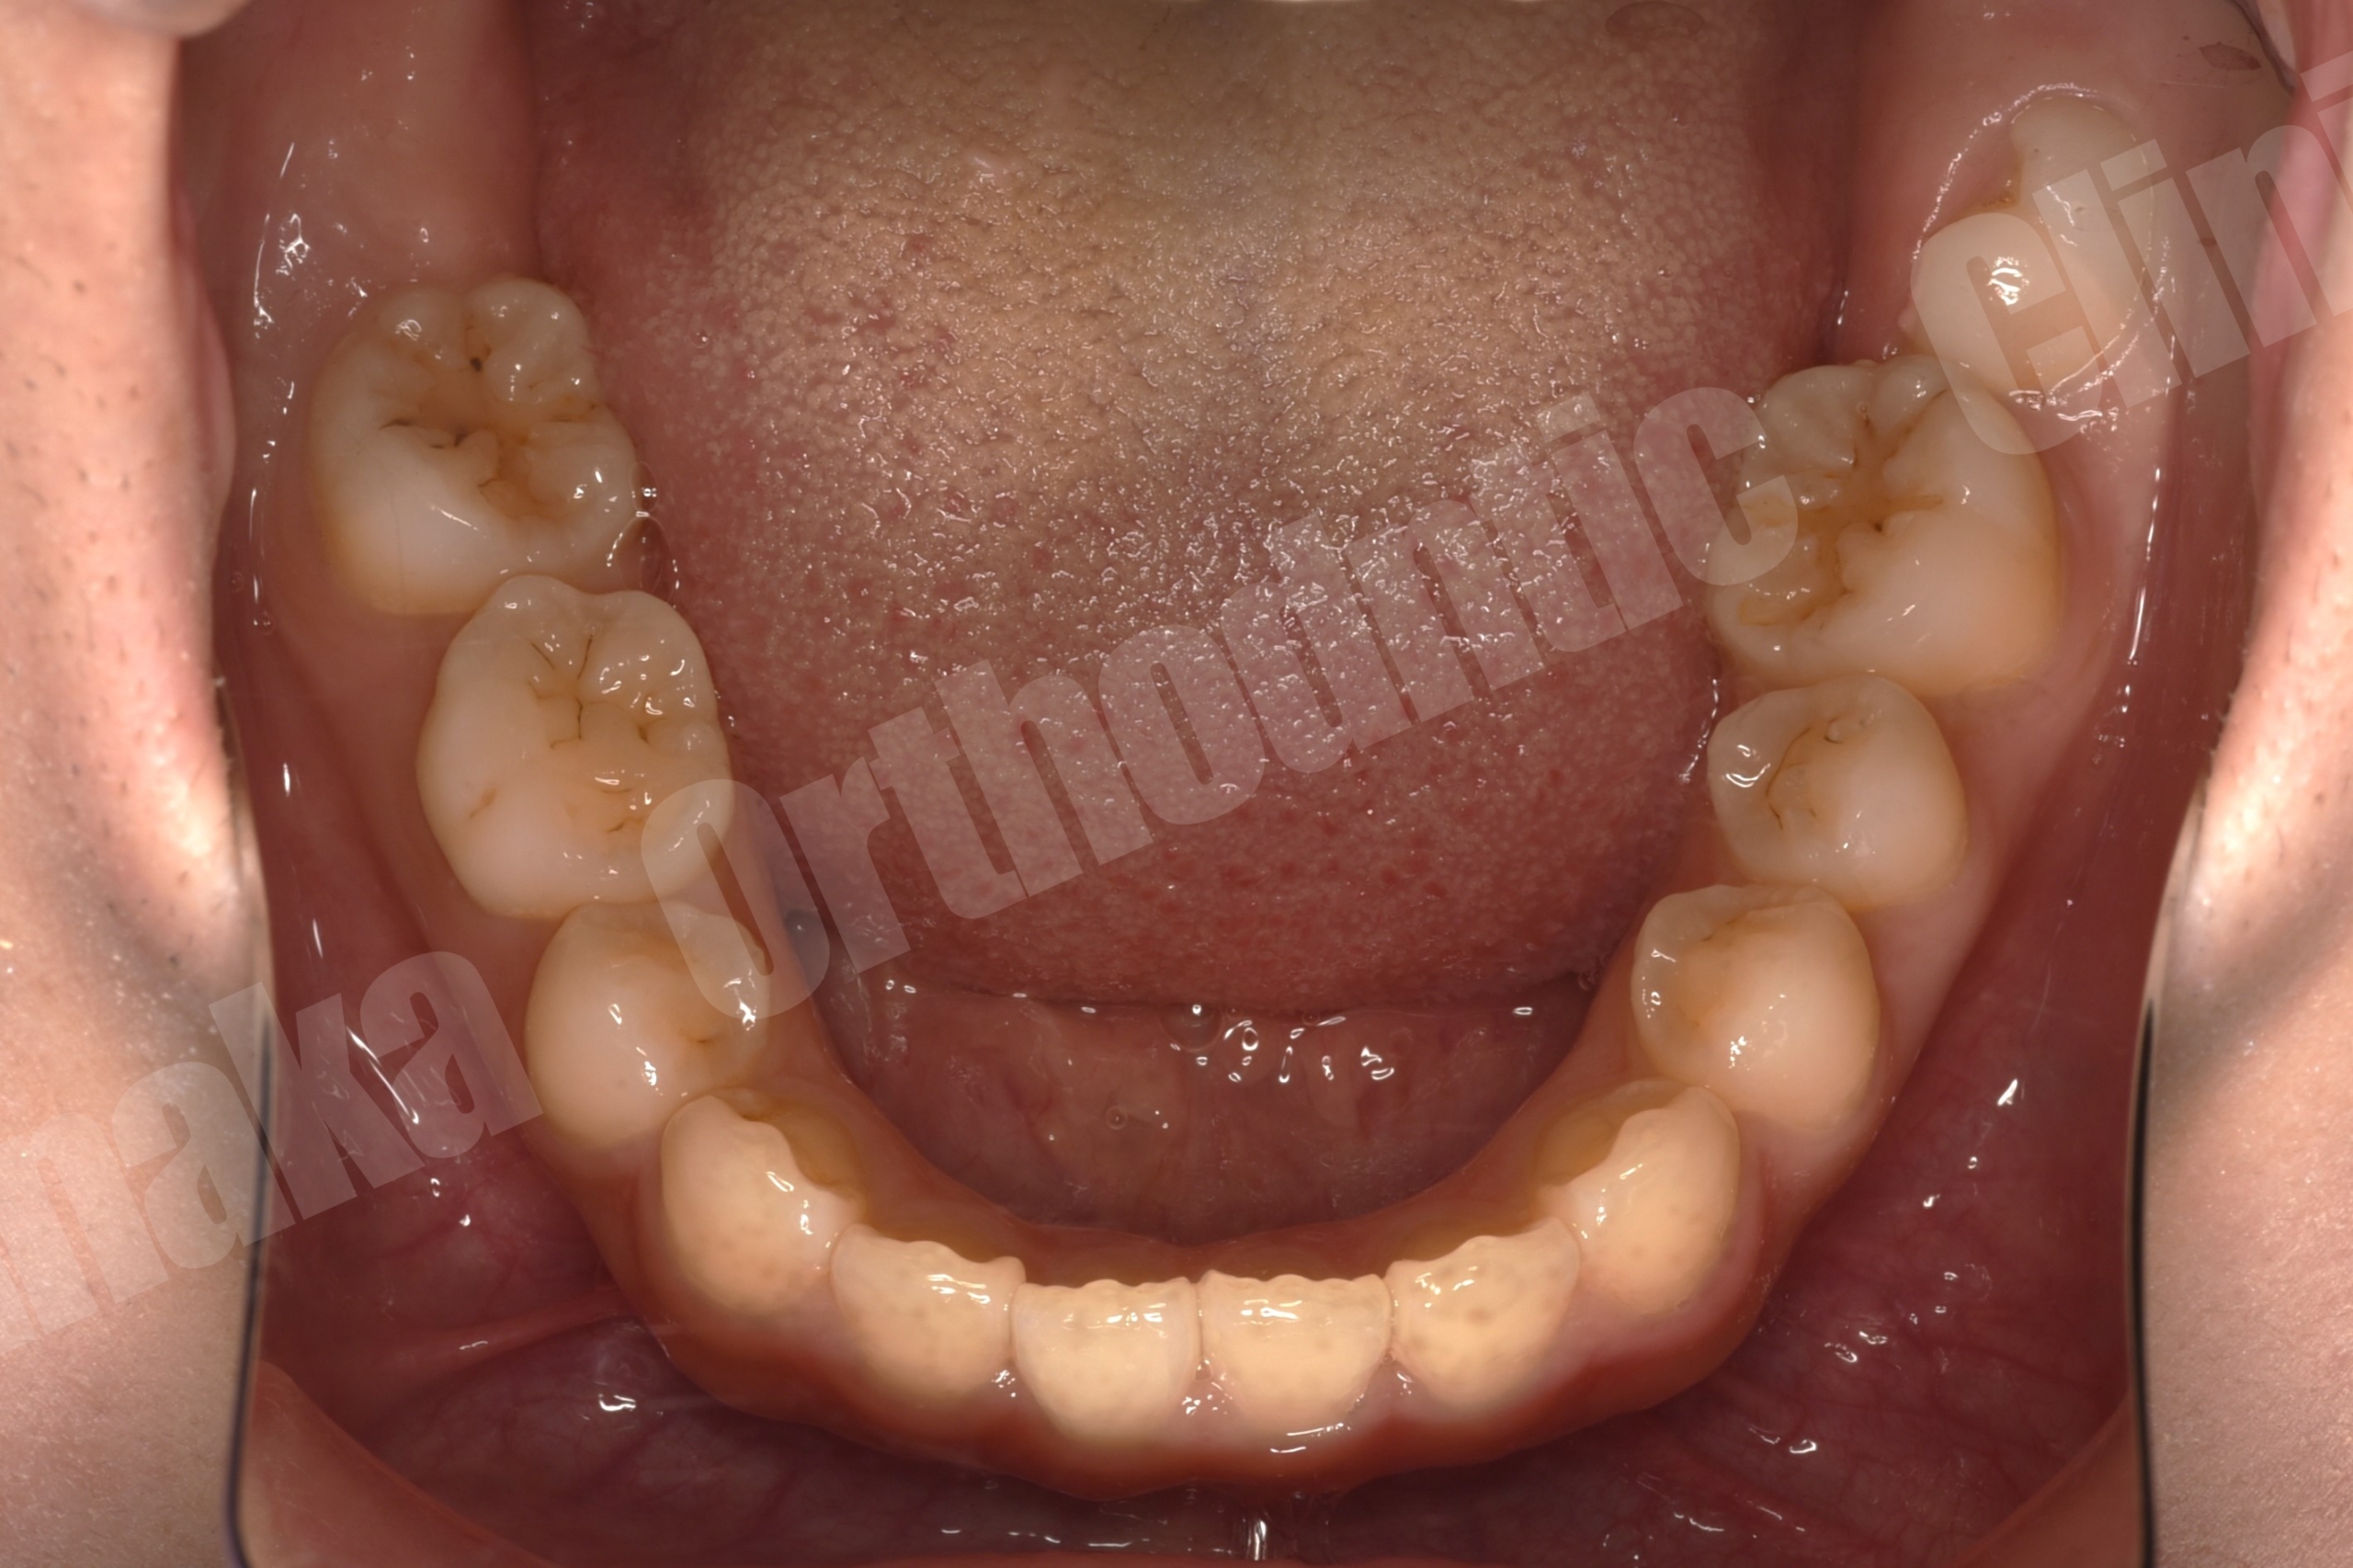

初診時の診査では、上顎前歯が唇側に傾斜しており、前歯の水平被蓋(オーバージェット)が大きい状態でした。そのため口元の突出感が認められ、前歯部は十分に噛んでいない状態でした。また下顎正中は左側へ偏位しており、右下E(乳臼歯)の残存と5番の先天欠如、さらに下顎両側7番の位置異常も確認されました。さらに患者様は10代半ばの頃に一度、非抜歯でマルチブラケット矯正を受けており、その影響もあって上顎中切歯には歯根吸収が生じ、歯根がやや短くなっている所見も認められました。

そこで治療では上下歯列に唇側マルチブラケット装置を装着し、歯列全体の排列を行いました。上顎前突を改善するため上顎両側4番を抜歯し、前歯を後退させて口元のバランスを整える計画としました。さらに下顎正中の改善のため右下Eを抜歯し、約11mmある乳臼歯部のスペース閉鎖を行う計画としました。このスペース閉鎖には矯正用アンカースクリューを使用し、右側6番・7番を近心移動させる必要があります。また治療途中で萌出してくる右下7番の位置を適切にコントロールすることも重要なポイントとなります。

今回の症例では、11mmという比較的大きなスペース閉鎖に加え、治療途中で萌出してくる7番のコントロールも必要となるため、通常より難易度の高い治療となりました。そのため治療期間は通常よりやや長くなる可能性を考慮し、2年以内での治療終了を目標として治療を開始しました。

結果として歯の移動は順調に進み、約1年8か月で治療を終了することができました。気になっていた上顎前歯の突出感と側貌は改善し、前歯の咬み合わせも回復しました。また右下乳臼歯部のスペースを閉鎖することで、将来的にインプラントなどの補綴処置が必要になる可能性も回避することができました。